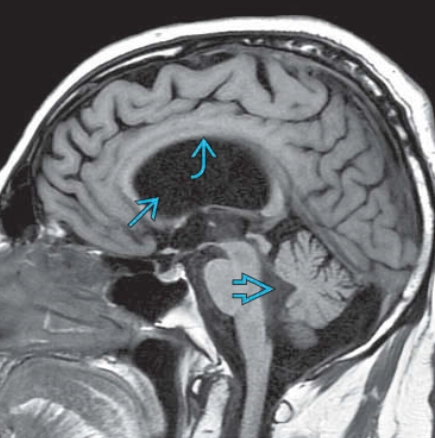

Hẹp cống não (Aqueductal Stenosis)

16/03/2026